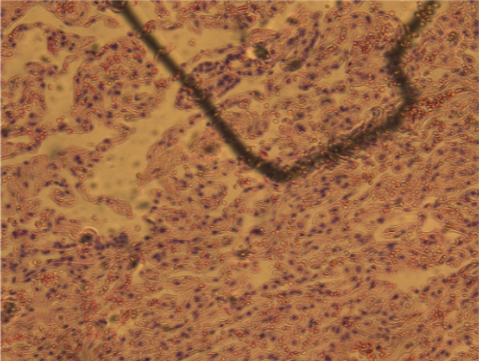

器官组织切片

![]() | ![]() | |

普通彩色相机采图结果 | 大恒图像相机色彩优化后 |